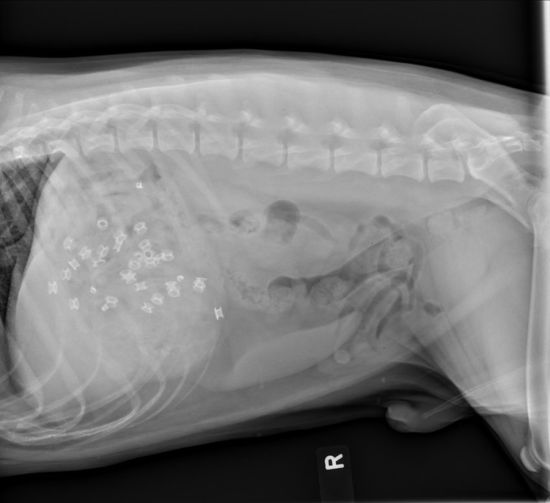

报道称,这只名叫文斯(Vince)的4岁串种犬胃口很好,但很显然选错了食物。它的主治医生接受采访时表示:“通过x光片可以很清楚地看到它胃内的皮革,由于数量众多堆积在胃肠内,已经危及到了它的生命安全。”

据悉,为了能够取出皮革,医生必须对文斯进行手术,而它胃部的x光片却很有可能出名:美国的一本兽医杂志每年都会刊登各种动物不可思议的x光片,2014年最有名的一张来自于一只吞掉了30枚石块的青蛙。